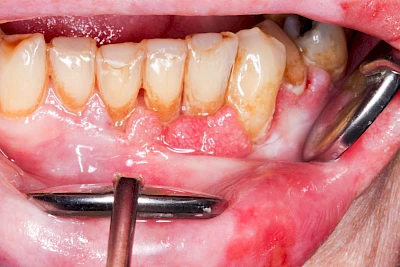

Bakterien in den Zahnbelägen greifen neben den Zähnen auch das Zahnfleisch (Gingiva) und den gesamten Zahnhalteapparat (Parodont) an. Der Körper reagiert mit einer Entzündung, sichtbar als Rötung und Schwellung. Meist blutet das Zahnfleisch z .B. beim Essen oder auch beim Putzen der Zähne.

Ist zunächst nur das Zahnfleisch von der Entzündung betroffen, spricht man von Gingivitis. Später, wenn auch der Knochen um die Zähne herum entzündet ist, spricht man von einer Parodontitis. Bei der Parodontitis wird der Knochen nach und nach abgebaut und das Zahnfleisch zieht sich zurück. Die Zahnhälse und Zahnwurzeloberflächen liegen mehr und mehr frei. Die Zähne werden zunehmend lockerer und fallen schließlich aus.